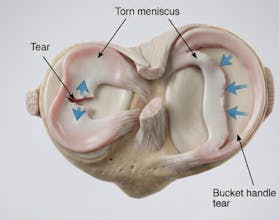

Natomy AI creates high-quality, medically accurate images and videos of human anatomy. Start with image-to-image: upload any low-quality photo, real image, or animation, and Natomy transforms it into an ultra-realistic anatomical visual. Unlike other AI tools that get anatomy wrong, Natomy is accurate every time—and fully editable by simply highlighting what you want changed and describing the update. Text-to-video launches in 2 weeks.